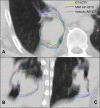

Purpose: Respiratory motion of locally advanced non-small cell lung cancer (LA-NSCLC) adds to the challenge of targeting the disease with radiotherapy (RT). One technique used frequently to alleviate this challenge is an internal gross tumor volume (IGTV) generated from manual contours on a single respiratory phase of the 4DCT via the aid of deformable image registration (DIR)-based auto-propagation. Through assessing the accuracy of DIR-based auto-propagation for generating IGTVs, this study aimed to identify erring characteristics associated with the process to enhance RT targeting in LA-NSCLC.

Methods: 4DCTs of 19 patients with LA-NSCLC were acquired using retrospective gating with 10 respiratory phases (RPs). Ground-truth IGTVs (GT-IGTVs) were obtained through manual segmentation and union of gross tumor volumes (GTVs) in all 10 phases. IGTV auto-propagation was carried out using two distinct DIR algorithms for the manually contoured GTV from each of the 10 phases, resulting in 10 separate IGTVs for each patient per each algorithm. Differences between the auto-propagated IGTVs (AP-IGTVs) and their corresponding GT-IGTVs were assessed using Dice coefficient (DICE), maximum symmetric surface distance (MSSD), average symmetric surface distance (ASSD), and percent volume difference (PVD) and further examined in relation to anatomical tumor location, RP, and deformation index (DI) that measures the degree of deformation during auto-propagation. Furthermore, dosimetric implications due to the analyzed differences between the AP-IGTVs and GT-IGTVs were assessed.